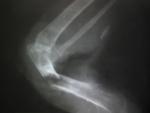

Рентген плеча сверху

post-55598-1478519300_thumb.jpg

Рентген снизу

post-55598-1478519335_thumb.jpg

2.Перелом простой, со смещением,на снимке вроде как закрытый. Или вы кости видите?

Мне не нравится зотя активного затемнения трубчатой части костей- это скорее всего зона некроза.

По уму- такой перелом под остеосинтез.т.к. косточки толстые,спицу вставить можно. НО! Повреждение старое...

Перелом открытый. Вот на фото видно кость.

Затемнение - это открытый перелом и открытая рана (в области мышц затемнение). Спицу самой не вставишь, а в птицах ветврачей нет,только по кошкам и собакам.